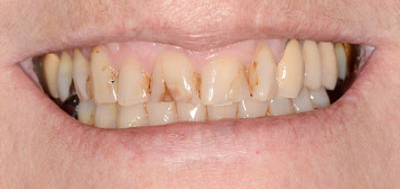

Les dents du secteur antérieur se chevauchent et 3 dents dévitalisées ont pris une teinte orangée. Le motif de la consultation est esthétique.

Les 4 facettes sont conçues, usinées et polies en 3 heures.

Collage des facettes. Les 4 facettes et le remodelage de la 12 ont évité l’orthodontie et la mutilation des dents en vue de la réalisation de couronnes périphériques complètes.